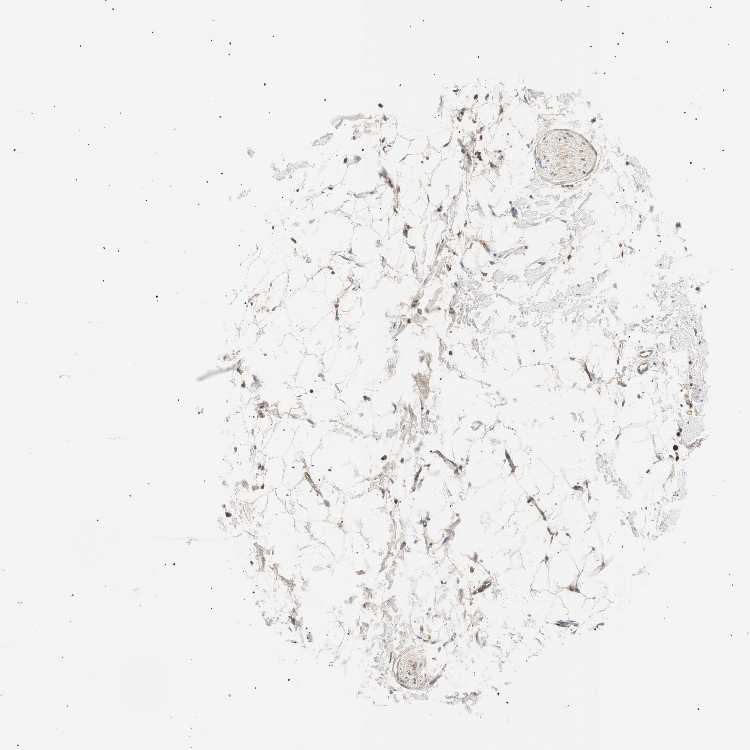

ADIPOSE TISSUE - Antibody stainingi

Antibody staining in the annotated cell types in the current human tissue is reported as not detected, low, medium, or high, based on conventional immunohistochemistry profiling in selected tissues. This score is based on the combination of the staining intensity and fraction of stained cells.

Each image is clickable and will lead to virtual microscopy that enables deeper exploration of all samples and also displays staining intensity scores, fraction scores and subcellular localization as well as patient and tissue information for each sample.

Antibody HPA006804

Adipocytes Medium